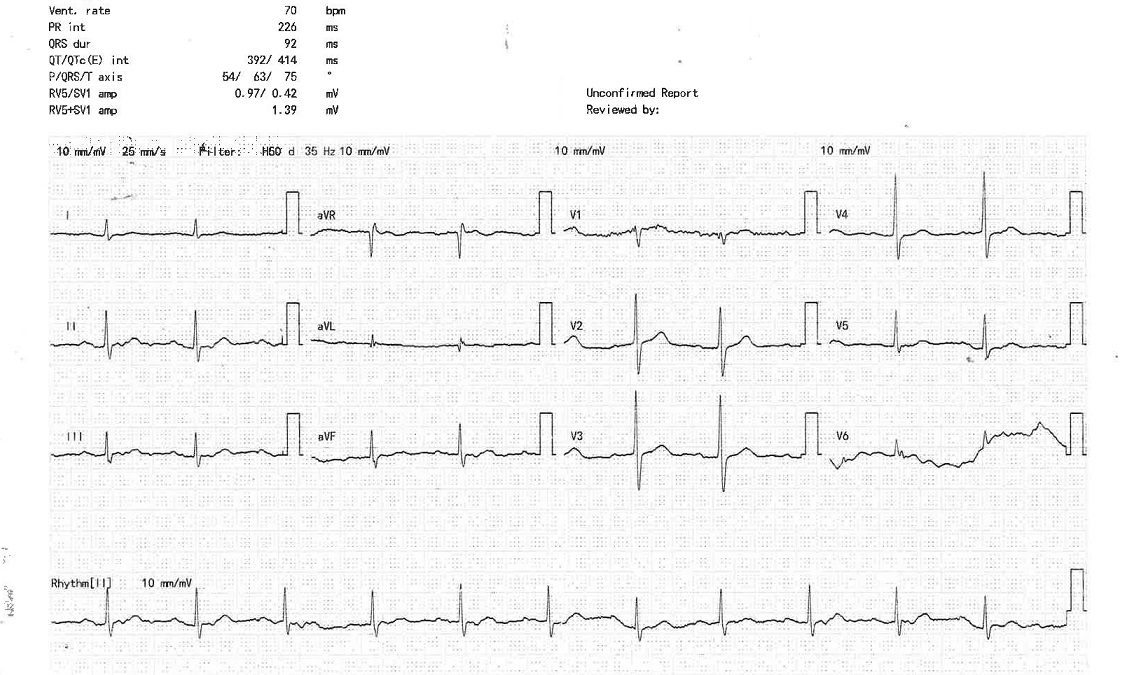

Relevant Test Results Prior to Catheterization

The baseline ECG was normal. The Trop-I: 394 ng/mL (high)